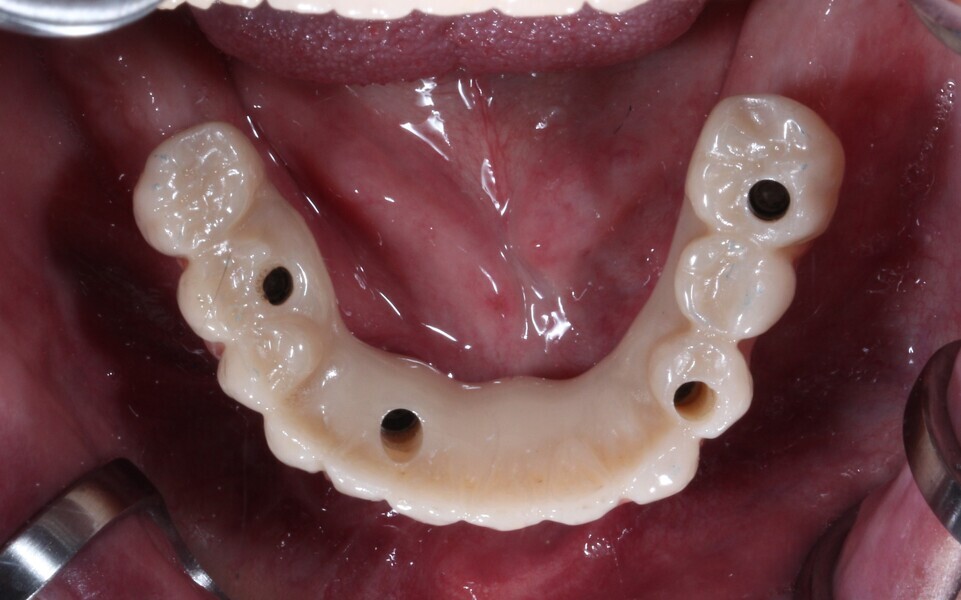

Fig. 21: Final maxillary prosthesis, occlusal view.

Fig. 22: Final mandibular prosthesis, occlusal view.